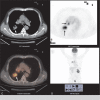

Endobronchial hamartoma mimicking malignant lung tumor contralateral endobronchial metastasis: A case report

Patient concerns: We report a rare case of endobronchial hamartoma in which the clinical symptoms and imaging overlapped strongly with malignant lung tumor contralateral endobronchial metastasis.

Diagnoses: Endobronchial hamartoma coexisting with a malignant lung tumor.

Interventions: Fiberoptic bronchoscopy was conducted, and the pathologic diagnosis was hamartoma. A second fiberoptic bronchoscopy was conducted, and fine-needle aspiration cytology of the enlarged lymph nodes indicated squamous cell carcinoma.

Outcomes: The clinical symptoms were relieved, and the treatment options were docetaxel, cis-dichlorodiamineplatinum, and endostatin.